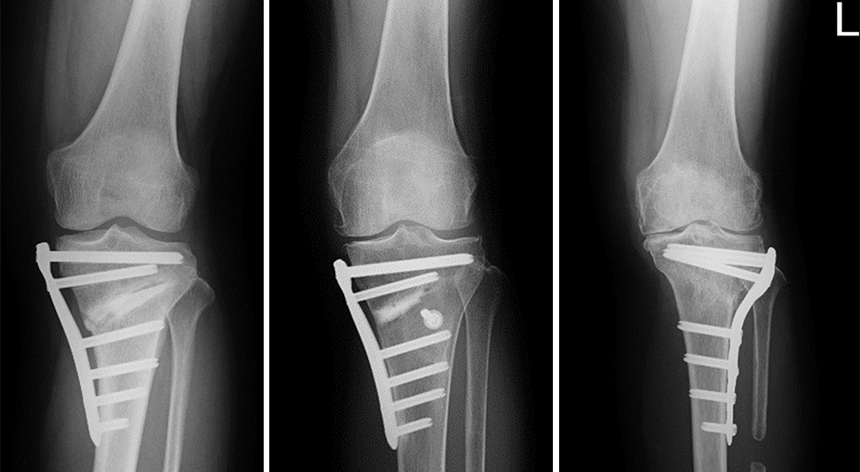

③ 脛骨高位骨切り術 (High Tibial Osteotomy:HTO)ほか

O脚変形がつよく、膝関節の内側のみに変形がある早期(~中期)変形性膝関節症の方で、スポーツ継続希望など活動性の高い方や人工関節手術を検討するには年齢的に若い方に対しておこないます。HTOの手術の中でも、脛骨近位部の変形矯正の程度に応じて、骨切りの方法を使い分けて手術を行っています。

HTOに代表される膝周囲骨切り術(AKO)の分野は,近年様々な術式・工夫が開発され、あわせて専用のプレートも開発され、O脚からX脚まで対応できるように進化しています。